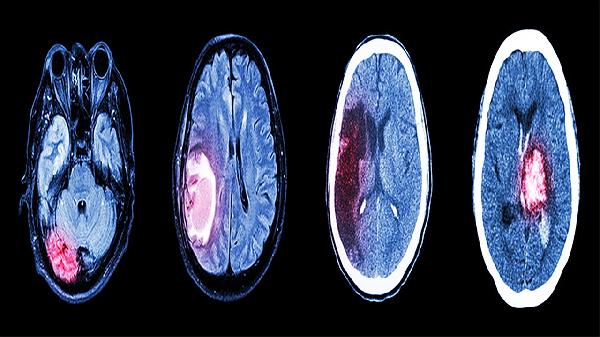

如果脑垂体异常是由于腺瘤(通常是良性肿瘤)引起,会因为压迫周围组织影响神经功能,特别是视力受损。常见症状包括头痛、视力模糊、视觉缺损等,尤其是双眼外侧视野丧失,称为“双颞侧偏盲”。

建议与治疗:需要进行磁共振成像(MRI)或CT扫描明确肿瘤类型和范围。治疗可能包括: